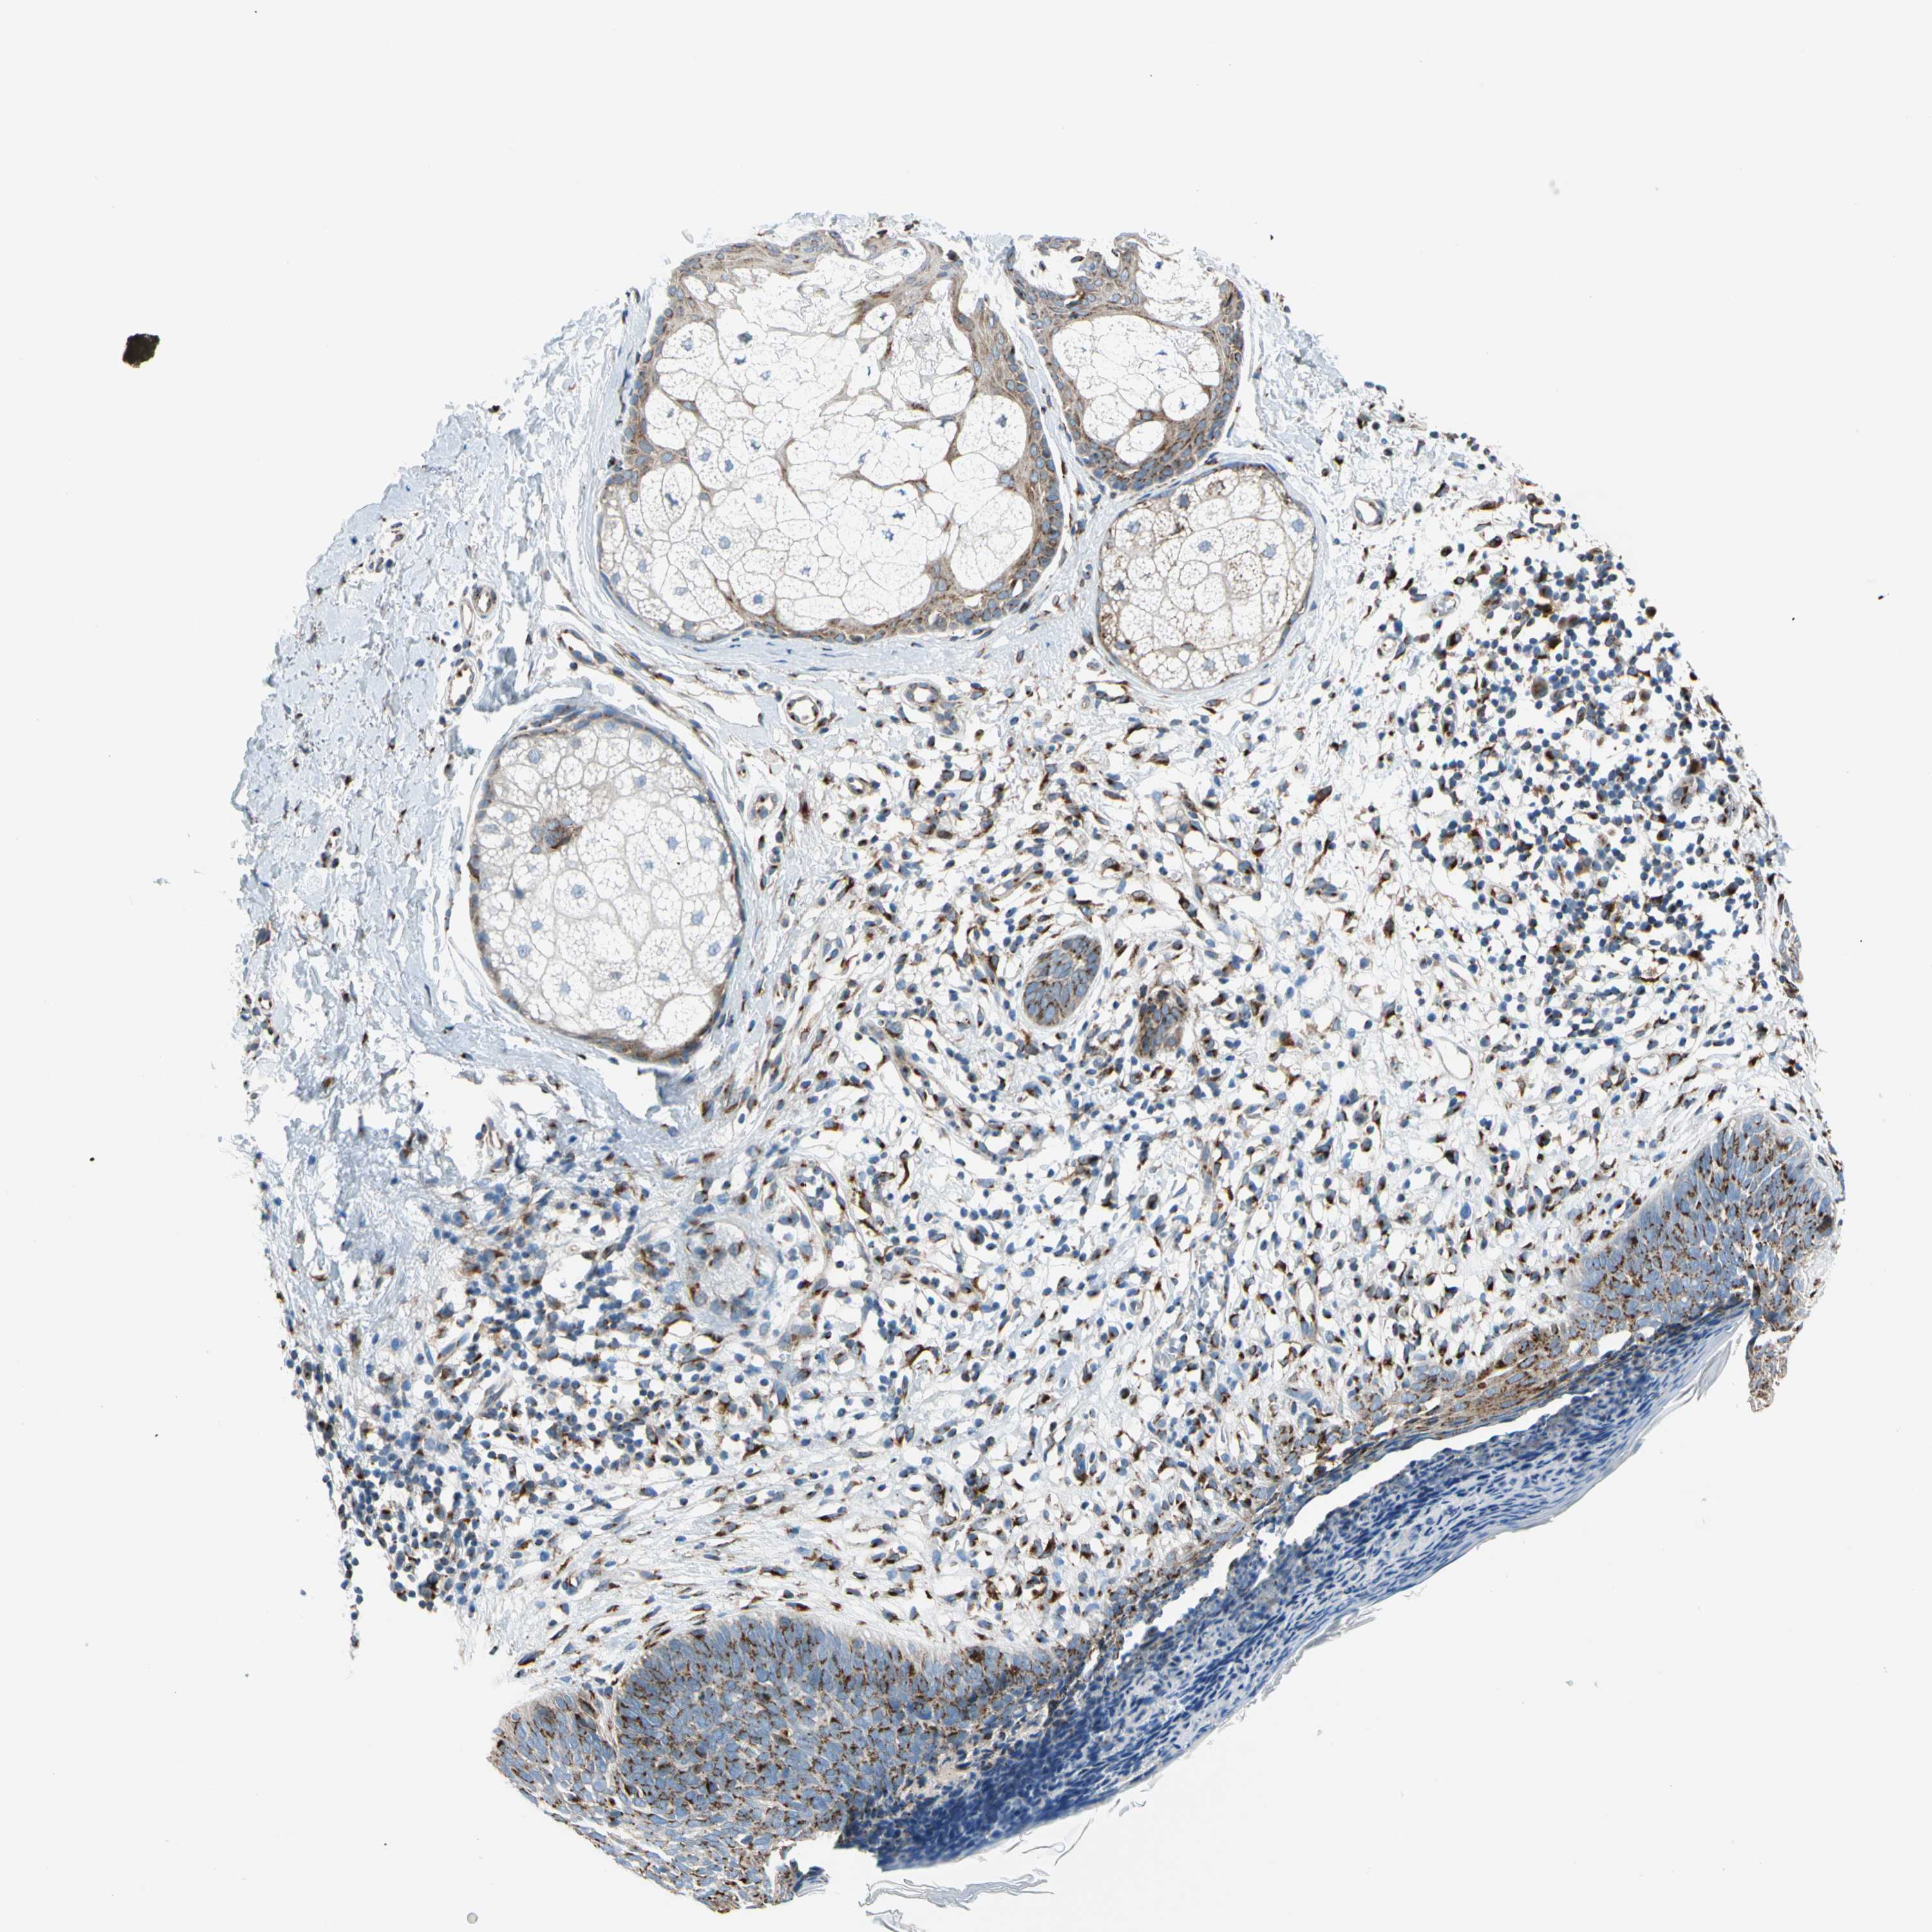

SKIN CANCER - Protein expressioni

A mouse-over function shows sample information and annotation data. Click on an image to view it in a full screen mode. Samples can be filtered based on level of antibody staining by selecting one or several of the following categories: high, medium, low and not detected. The assay and annotation is described here.

Each image is clickable and will lead to virtual microscopy that enables deeper exploration of all samples and also displays staining intensity scores, fraction scores and subcellular localization as well as patient and tissue information for each sample.

Antibody HPA008176

Staining

Medium

Intensity

Moderate

Quantity

75%-25%

Location

Cytoplasmic/membranous

Basal cell carcinoma